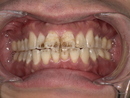

6歳女の子 抜けずに残っている乳歯を抜いて永久歯が正しく生えるスペースを確保した症例

こんにちは、名古屋市天白区の小児歯科・歯医者・歯科のイナグマ歯科です。 子どもの歯は成長ととも...